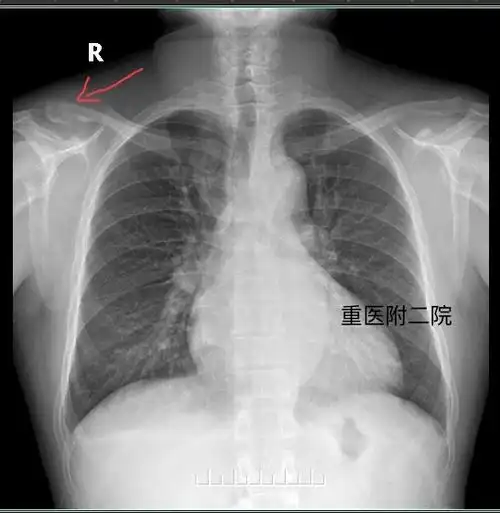

右锁骨中段骨折

胸部正侧位:右侧锁骨肩峰端及双侧锁骨远段异常改变,右侧肩锁关节间隙

x线显示锁骨远端骨折